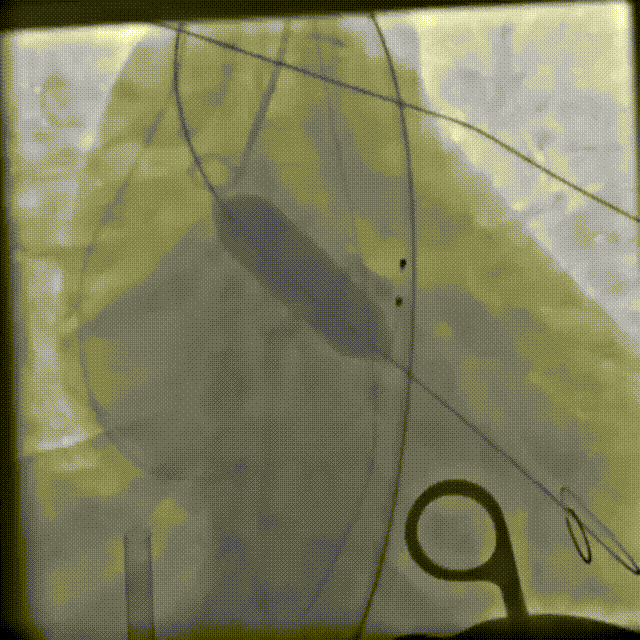

TF25号瓣膜初始定位

全展开评估,瓣膜位置可,形态可见压缩

左侧位评估

瓣膜瓣下2mm左右